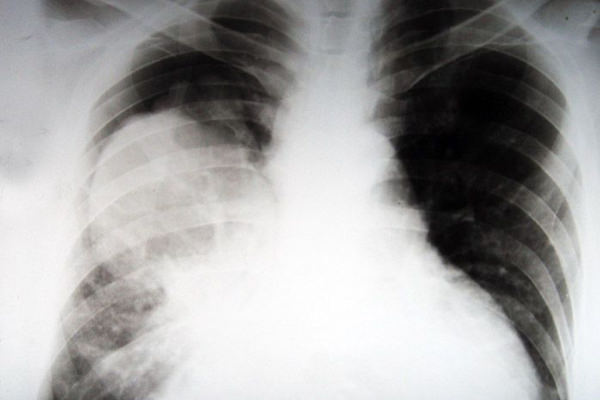

Статистика рака легких (аденокарциномы) у курильщиков

Статистические данные исследований говорят о том, что именно курение становится причиной развития рака бронхолегочной системы. И связано это в большей степени с канцерогенами сигарет: попадая в организм постоянно и в больших количествах, накапливаясь там, химические соединения дыма и продуктов сгорания приводят сначала к нарушениям работы слизистой бронхов, их эпителиального слоя и железистой ткани. Затем развиваются хронические нарушения процессов клеточного образования и кровоснабжения, а далее начинаются процессы деформации клеток, замещения нормального цилиндрического эпителия плоским многослойным, патологических изменений железистой ткани. Это приводит к образованию плоскоклеточного рака (слизистая рта и гортани) и аденокарциномы (рак легких).

В 90% случаев установленного рака легких выясняется, что пациенты онкологической пульмонологии — курильщики. Это явно указывает на курение, как на одну из самых значительных причин возникновения ракового заболевания. А уж в условиях современной экологической обстановки курение становится настоящей атомной бомбой, запускающей процессы развития рака. Выхлопы автомобилей и выбросы промышленных предприятий, электромагнитное и радиационное излучение, пыль, бактерии и вирусы, различные заболевания бронхолегочной системы (например, заболеваемость астмой и ХОБЛ растет год от года) — на этом фоне курение становится терминальным фактором-провокатором рака.

По данным медицинской статистики, в городах раком легкого заболевают примерно 12,7% мужского населения, там бронхогенный рак выходит на 3-4 место по частоте заболеваемости. В крупных же городах с развитой промышленностью частота выявления рака составляет 18% — это уже первое место в общей структуре онкопатологий. Оценивая данные статистики, нужно также помнить, что примерно 30% случаев рака легких и смерти от него остаются не выявленными, человек считает, что болен тяжелой астмой, туберкулезом, их же указывают в причинах смерти.

Каждый год к числу уже страдающих раком легких прибавляется 1 миллион человек с впервые диагностированным этим заболеванием, из них без лечения 90% умрут в течение двух ближайших лет и всего лишь 40% останутся в живых через 5 лет, несмотря на проводимое лечение. Подсчитано, что из ста курильщиков у 18 мужчин и 12 женщин обязательно разовьется рак легкого. И у 90% умерших от него причина развития данной патологии — курение.